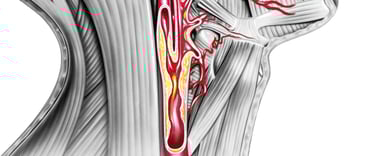

La ecografía de troncos supraaórticos (TSA) permite explorar las arterias carótidas y vertebrales, que son las principales vías de entrada de sangre al cerebro. Es una prueba rápida, indolora y no invasiva, que detecta placas de colesterol, estrechamientos (estenosis) u obstrucciones que pueden provocar un ictus o accidente cerebrovascular. Se trata también de una prueba esencial para el diagnostico de las causas tras un ictus isquémico.

Ecografía Doppler transcraneal en Castellón: ¿Por qué realizar la Eco-Doppler transcraneal junto a la carotídea?

Realizar únicamente la ecografía de cuello puede dar una falsa seguridad. Por un lado, muchas placas de ateroma (colesterol) no son visibles mediante ecografía directa y requieren del estudio intracraneal de los signos indirectos. Por otro lado, al alteraciones se encuentran dentro del cráneo y no serían visibles sin el doppler transcraneal. Por ello, en la Clínica Diago Muñoz siempre completamos la exploración con este estudio intracraneal.

El neurólogo es el especialista más indicado para realizar esta prueba, porque integra los hallazgos de la ecografía carotídea y transcraneal con la historia clínica, los síntomas y los factores de riesgo vascular, ofreciendo así una valoración global y precisa.